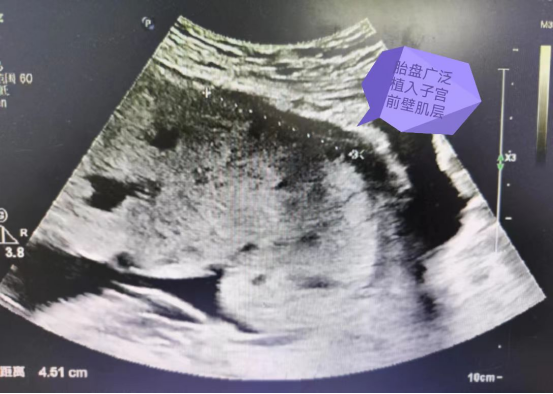

孕早期行NT彩超提示胎盘位于子宫前壁,胎盘下缘达宫颈内口,胎儿系统超声时提示胎盘下缘位于宫颈内口边缘,后多次彩超均提示胎盘下缘覆盖宫颈内口。

医院彩超提示横位,胎盘位于子宫前壁,下缘覆盖宫颈内口,下段胎盘后方与子宫肌层间无分解,考虑胎盘植入,完善磁共振检查提示植入待排,并建议36周计划入院终止妊娠。

①胎盘下缘完全覆盖宫颈内口

②胎盘后间隙与子宫肌层间无明显界限,未见明显肌层声像

③实质内见多个无回声区